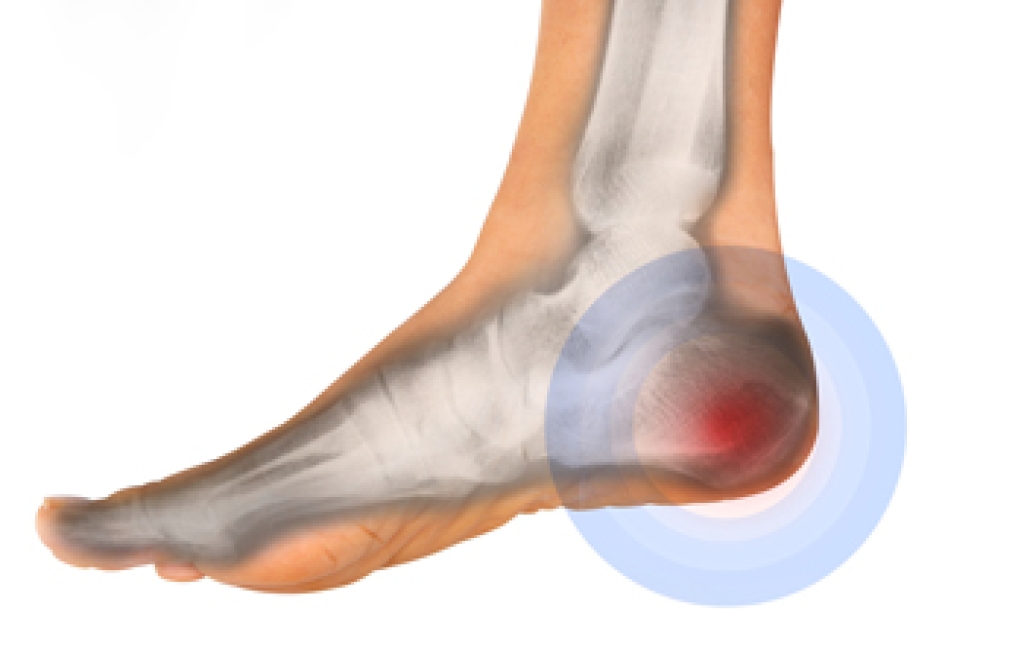

A stress fracture is a common athletic injury. It often involves the long bones in the foot that are known as the metatarsal bones. When a stress fracture occurs, which is also referred to as a hairline fracture, it can cause pain and discomfort. It is often difficult to walk on the affected foot, and relief may come from elevating the foot. It can happen when runners increase their speed and distance too fast. Additionally, people who run for long distances at a time may experience a stress fracture. Wearing shoes that fit correctly may decrease the risk of getting this type of fracture. Some people have existing medical conditions that may increase the risk of getting a stress fracture. These can include osteoporosis, arthritis, diabetes, or a vitamin deficiency. A diagnosis is typically performed by having an X-ray taken, and then proper treatment measures are taken. If you feel you have a stress fracture, it is strongly suggested that you schedule an appointment with a podiatrist who can help you to manage this ailment.

Stress fractures are the result of repetitive force being placed on the bone. Since the lower leg and feet often carry most of the body’s weight, stress fractures are likely to occur in these areas. If you rush into a new exercise, you are more likely to develop a stress fracture since you are starting too much, too soon. Pain resulting from stress fractures may go unnoticed at first, however it may start to worsen over time.

Stress fractures do not always heal properly, so it is important that you seek help from a podiatrist if you suspect you may have one. Ignoring your stress fracture may cause it to worsen, and you may develop chronic pain as well as additional fractures.